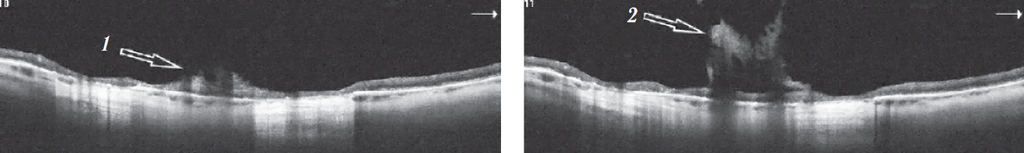

Рис. 8. Оптическая когерентная томограмма периферической сетчатки левого глаза. Срез через очаг хориоретинальной дистрофии: 1 — место тракции сетчатки тяжем фиксированного и уплотнённого стекловидного тела (2)

Fig. 8. Optical coherence tomography of the peripheral retina of the left eye. Scan through the focus of chorioretinal dystrophy area: 1 – retinal traction with a fixed and compacted vitreous band (2)